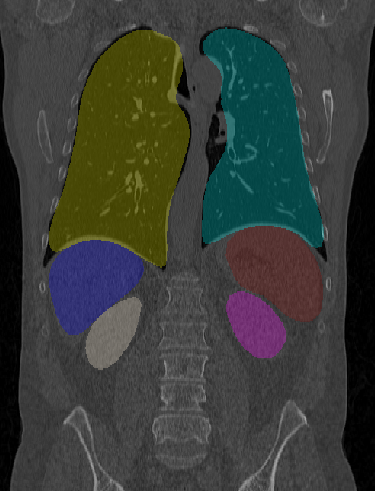

Figure 3: The result of multi-organ segmentation of a CT dataset (left), an example of the liver segmentation of a flat-panel CT scan of a liver (middle) and the warped visible human phantom overlay with a CT (right).